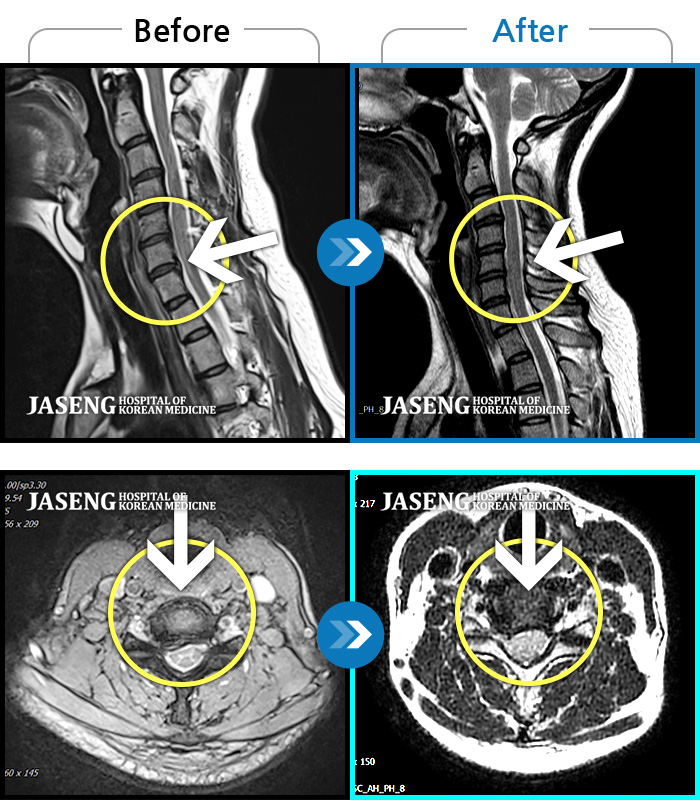

MRI 치료사례

처음 내원시 목에서 등으로 이어지는 통증 및 우측 팔 저림 증상이 심했고, 약간의 근력저하도 동반되어 일상생활이 어려운 상태였습니다.